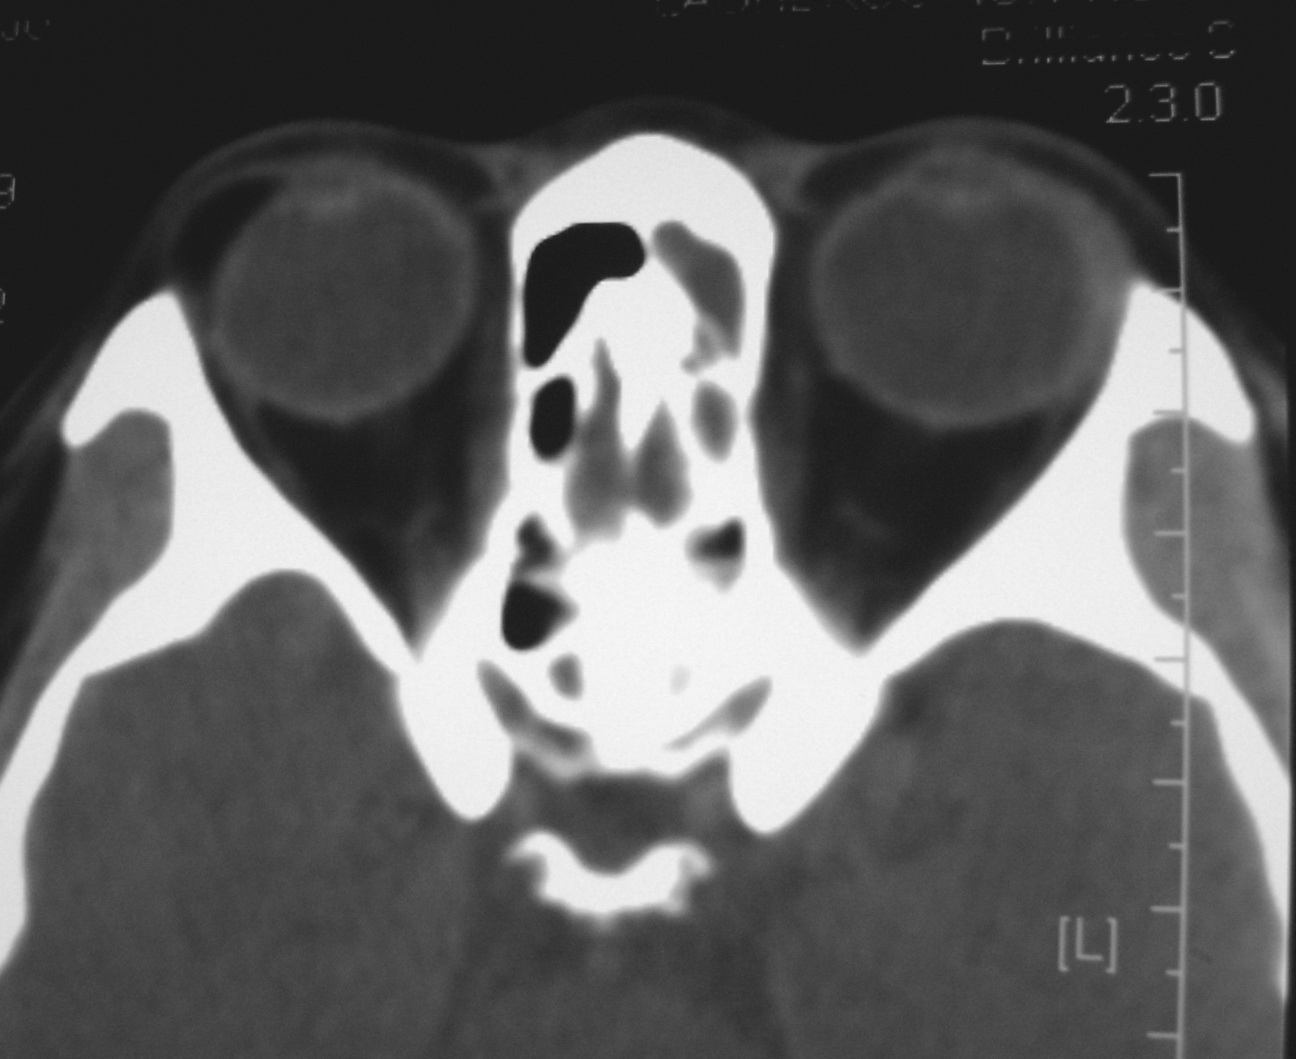

右侧眼眶脂肪瘤

女,34岁。右眼不适半年。

会员诊断:

表皮样囊肿、皮样囊肿、脂肪瘤

手术病理

:右侧眼眶

脂肪瘤

。